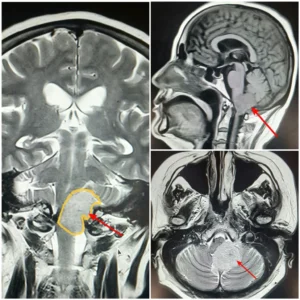

Менингиомани микрожарроҳлик усулида олиб ташлаш

Neurolife клиникасида менингиомани жарроҳлик йўли билан даволаш

Даволашнинг асосий босқичи микрожарроҳлик технологияларини қўллаган ҳолда менингиомани нейрохирургик даволаш бўлди. Аралашув доирасида менингиомада операция қуйидагилардан фойдаланган ҳолда амалга оширилди:

- операцион микроскоп;

- микрожарроҳлик асбоб-ускуналари;

- мия ва нерв тузилмалари функцияларини нейрофизиологик мониторинг қилиш.

Мия ўсмасини олиб ташлаш ҳаётий муҳим анатомик тузилмаларни сақлаган ҳолда ўсмани имкони борича тўлиқ кесиб олиш мақсадида амалга оширилди. Бундай ёндашув нейрохирургик операция асоратлари хавфини сезиларли камайтиради ва бемор учун прогнозни яхшилайди.